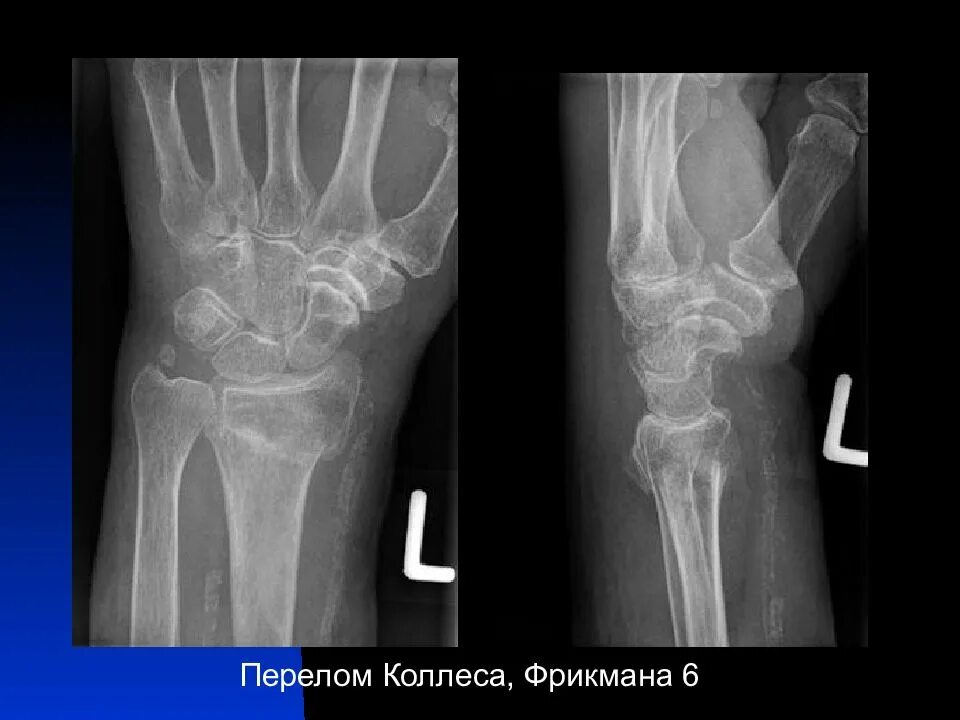

Ушиб лучезапястного